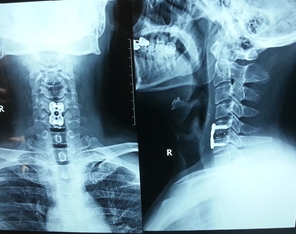

图2.颈椎病间盘摘除、CAGE植入、钢板内固定术后